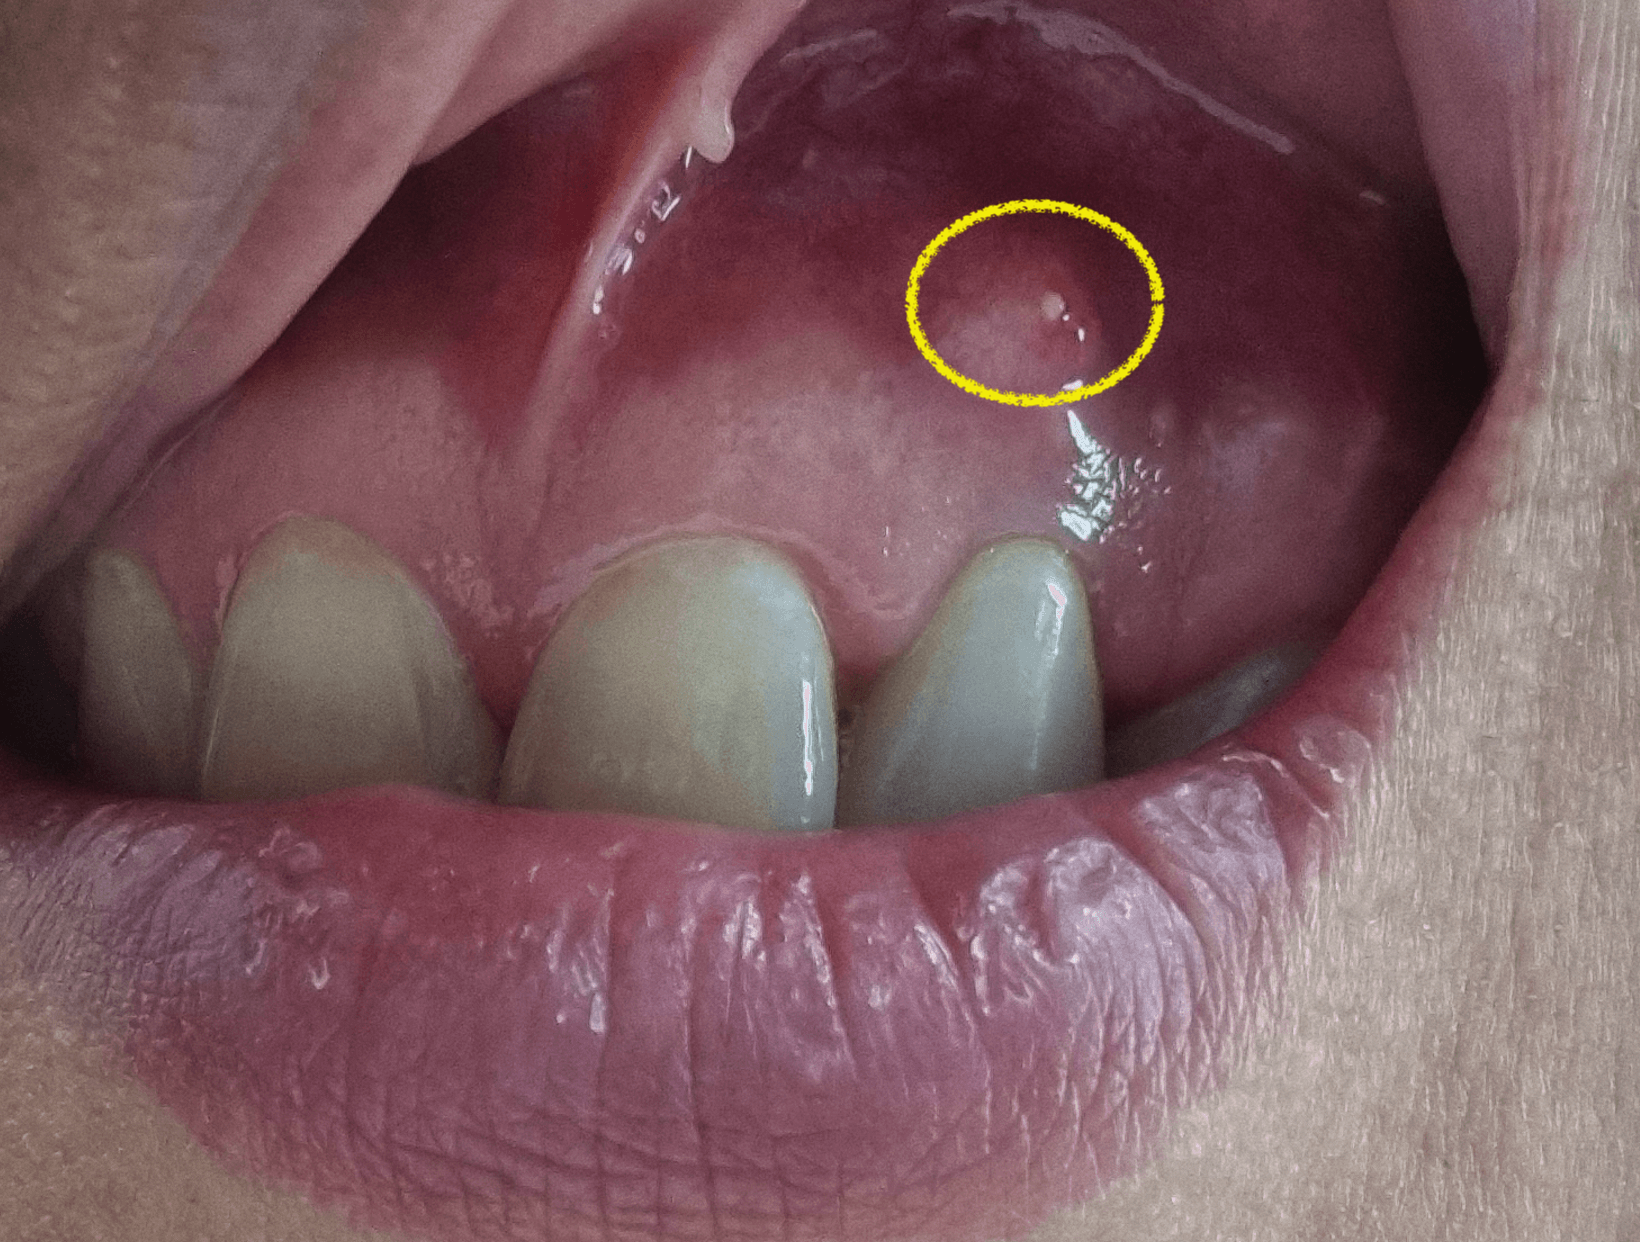

치근단절제술 수술을 한지 1년이 다된 지금 해당 앞니 치근단절제술을한 그부분에 잇몸이 다시 한번 불룩하게 티어 올라온것이 보였습니다. 그것은 딱봐도 염증이 차서 부어오른것이며, 저처럼 치근단절제술을 시행후 염증이 재발한 상황에 대한 내용을 의사가 아닌 환자로써 염증 재발 후기에 대한 정보를 공유 합니다.

치근단절제술후 염증 재발

1년정도 전에 치근단절제술을한 치아에서 다시 문제가 생겼습니다. 보통 3개월이 지나서 염증이 나오지 않으면 대부분 성공이라 생각하고 별일 없는이상 염증에 재발하지 않을거라 생각을 합니다.

그런데 저같은경우 기존에 염증 크기가 뼈이식을 할만큼 큰 낭종크기정도의 염증이라서 결국 염증이 완전하게 사라지지 않고 다시 다양한 사유로 인해 재발하게 된것 같다고 의사 선생님이 이야기를 했습니다.